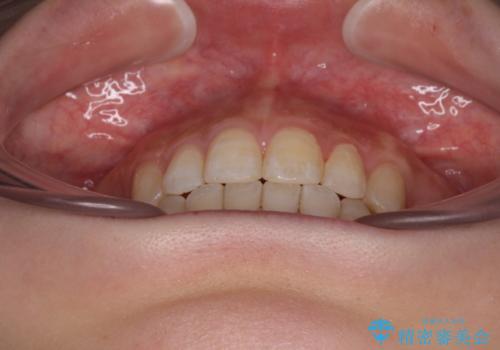

第二小臼歯抜歯はイレギュラーな治療手段であり、治療期間が延びる傾向にありますが、舌のトレーニングをしっかりと行ってくださり、2年弱という非常に短い期間で理想的な仕上がりを達成することができました。